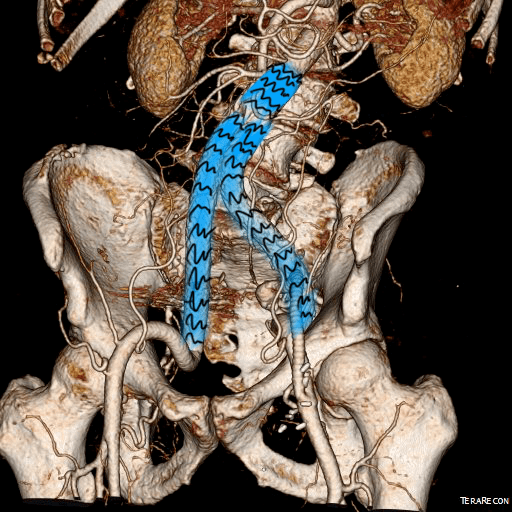

For example, take this patient who after EVAR of aortic aneurysm with AFX developed metachronous dilatation of the common iliac artery to 3.9cm with abdominal pain. The average diameter is 18.5mm. From the table, that rounds to 19mm corresponding to 283.53 square mm. If the internal iliac artery requires a 13mm graft, that is 132.73 square mm, the difference being 150.80 square mm. That corresponds to a 14mm diameter graft, but a slightly larger graft is preferred for oversizing. The external iliac artery is 8mm, and putting a 13mm Viabahn (largest available) in that would result in the B-infolding in the 8mm external iliac. Here, I bailed myself out by simply placing a 20mm AFX iliac limb extension, which by virtue of its design is resistent to infolding and tolerant of parallel grafts laid alongside in constricted channels. I found that the AFX iliac limb, a 20-13mm x 88mm length extension well suited for this.

The AFX graft limb seems to adapt to the presence of the parallel “sandwich” graft which is deployed second and ballooned last. In followup, there was shrinkage of the common iliac artery aneurysm sac and no endoleak.

Compared to my other parallel graft case treating a metachronous saccular common iliac aneurysm years after an EVAR with a Gore endograft (link), which by table calculation, resulted in 8% oversize in calculated areas, this particular technique with a large AFX graft and an appropriately sized Viabahn seemed to work well the setting of a previously placed AFX graft. It allows one to avoid hypogastric occlusion.